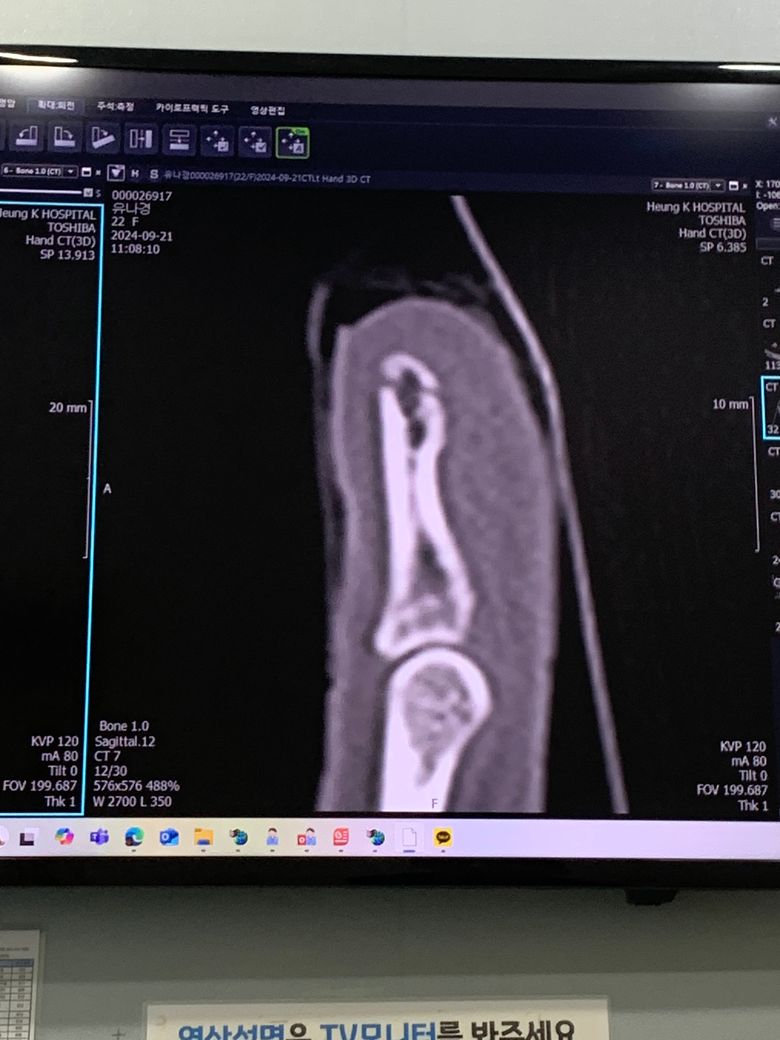

차문에 손 찍혔는데 이거 손톱 빠질까요ㅠ

차문에 엄청 쾅 손톱이 찍혀서 정형외과 가봤더니 손끝이 골절 됐다고 하더라고요 ㅠ

이거 손톱 안에 피도 뚝뚝 흐르는데 이거 손톱 빠질까요?

손톱손상 동반한 골절로 보입니다.

차문에 손을 심하게 찍혀서 손끝이 골절 되었고 손톱 아래 출혈 및 손톱아래 피가고이고 통증이 심하시고 공유해주신 사진을 보았을 때 손톱이 빠질 가능성이 높은 상태로 보입니다.

지금 상태로만 지켜보면 골절이 확실하고 손톱도 빠질 확률이 높습니다 차라리 손톱이 확실하게 빠지고 새로자라나는게 좋은상황일수도 있습니다 손톱보다는 골절을 치료하는것을 최우선적으로 생각하시길 바랍니다